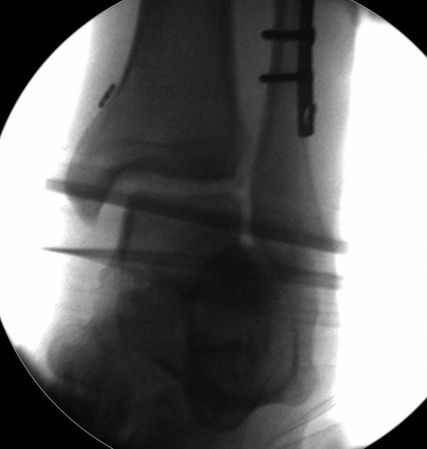

Die Kontrolle der Reposition und Stabilisierung wird unter exakter Einstellung des Sprunggelenks unter Bildwandler durchgeführt. Die Einbringung der Stellschraube erfolgt bei in Reposition temporär mit Bohrdraht fixierter Fibula, um Fehlzentrierung zu vermeiden.16